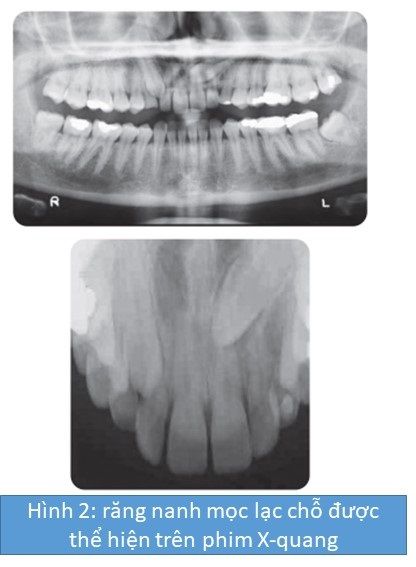

Bệnh nhân nữ 26 tuổi có tương quan răng cửa hạng I trên nền xương hạng I, kích thước dọc trung bình, phức tạp bởi các răng nanh hàm trên lạc chỗ phía khẩu cái. Bệnh nhân có độ cắn chìa 3mm, độ cắn trùm trung bình và hoàn toàn. Tương quan răng nanh: còn cả 2 răng nanh sữa hàm trên. Đường giữa: hàm trên lệch trái 2mm và hàm dưới lệch phải 1mm. Khớp cắn chức năng: chức năng nhóm.